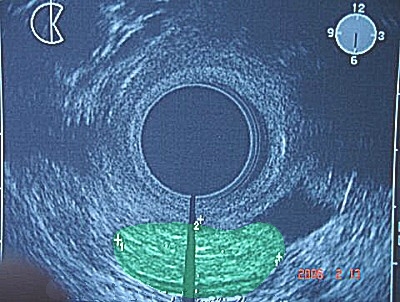

Abb. 3 bis 5: Durch die endo-vaginale Ultraschalluntersuchung ließ sich ein bösartiger Tumor - hier grün hinterlegt - darstellen, der sich ausschließlich auf die Scheidenhinterwand beschränkt hat. Abb. 3 bis 5: Durch die endo-vaginale Ultraschalluntersuchung ließ sich ein bösartiger Tumor - hier grün hinterlegt - darstellen, der sich ausschließlich auf die Scheidenhinterwand beschränkt hat.